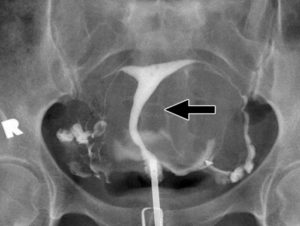

Сущность гистеросальпингографии состоит в заполнении маточной полости и ее труб особым веществом, которое называют контрастным. Вводят его с помощью катетера через влагалище.

Исследование проводят двумя способами: с помощью УЗИ и рентгена. Введенное вещество помогает выявить спайки маточных труб, воспалительные процессы, новообразования.

После обработки антисептиком с помощью катетера в полость матки направляют контрастное вещество. В тот момент, когда жидкость наполняет матку и трубы, делается ряд рентгенограмм, на которых зафиксированы результаты исследования.

Вначале жидкостью заполняют матку, делая нужное количество снимков. Затем, чтобы проверить проходимость труб, вводят дополнительное количество раствора.

Под напором краситель вытекает в трубы, а снимки фиксируют возможности их проходимости.

Результаты двух методик с достоверностью «расскажут» о состоянии матки и труб. Расшифровка снимков проста: проходимость маточных труб диагностируется в том случае, если введенное вещество, свободно циркулируя по матке и трубам, выходит в полость брюшины.

Снимок позволяет диагностировать и другие проблемы с женской репродуктивной системой:

- Спайки и полипы в маточной полости;

- Миома матки;

- Гидросальпингикс.

На рентгеновских снимках видно, как контрастное вещество проходит сквозь маточные трубы. Если жидкость заполнила трубы и попала в брюшную полость, врач удостоверяется в проходимости маточных труб. В том случае, если жидкость не полностью проникла в трубы и остановилась на определенном уровне, специалист подтверждает наличие непроходимости и назначает дальнейшее лечение.